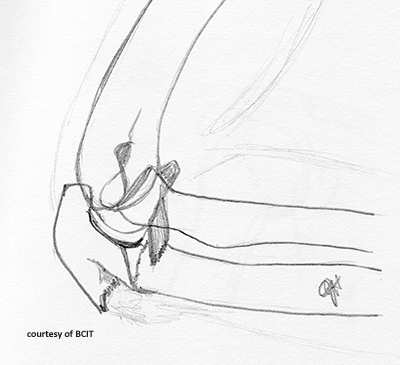

What injury is indicated by a visible fat pad (sail sign) on elbow X-ray?

Occult elbow joint fracture causing joint effusion.

What causes most posterior elbow dislocations, and what bone is often fractured?

FOOSH on an extended elbow; often involves coronoid process fracture.

What is the most common elbow fracture in adults?

Radial head fracture.

How are radial head fractures managed?

Splint/cast for simple fractures; surgery if severe. Early ROM exercises are critical.

What causes olecranon fractures and what muscle is involved?

Fall on flexed elbow; triceps muscle pulls fragment proximally.

What are complications of olecranon fractures?

Loss of full extension, scar tissue, non-union.

Why is the 'fat pad sign' important in elbow trauma?

It indicates joint effusion, often due to an occult intra-articular fracture even when the fracture line is not visible.